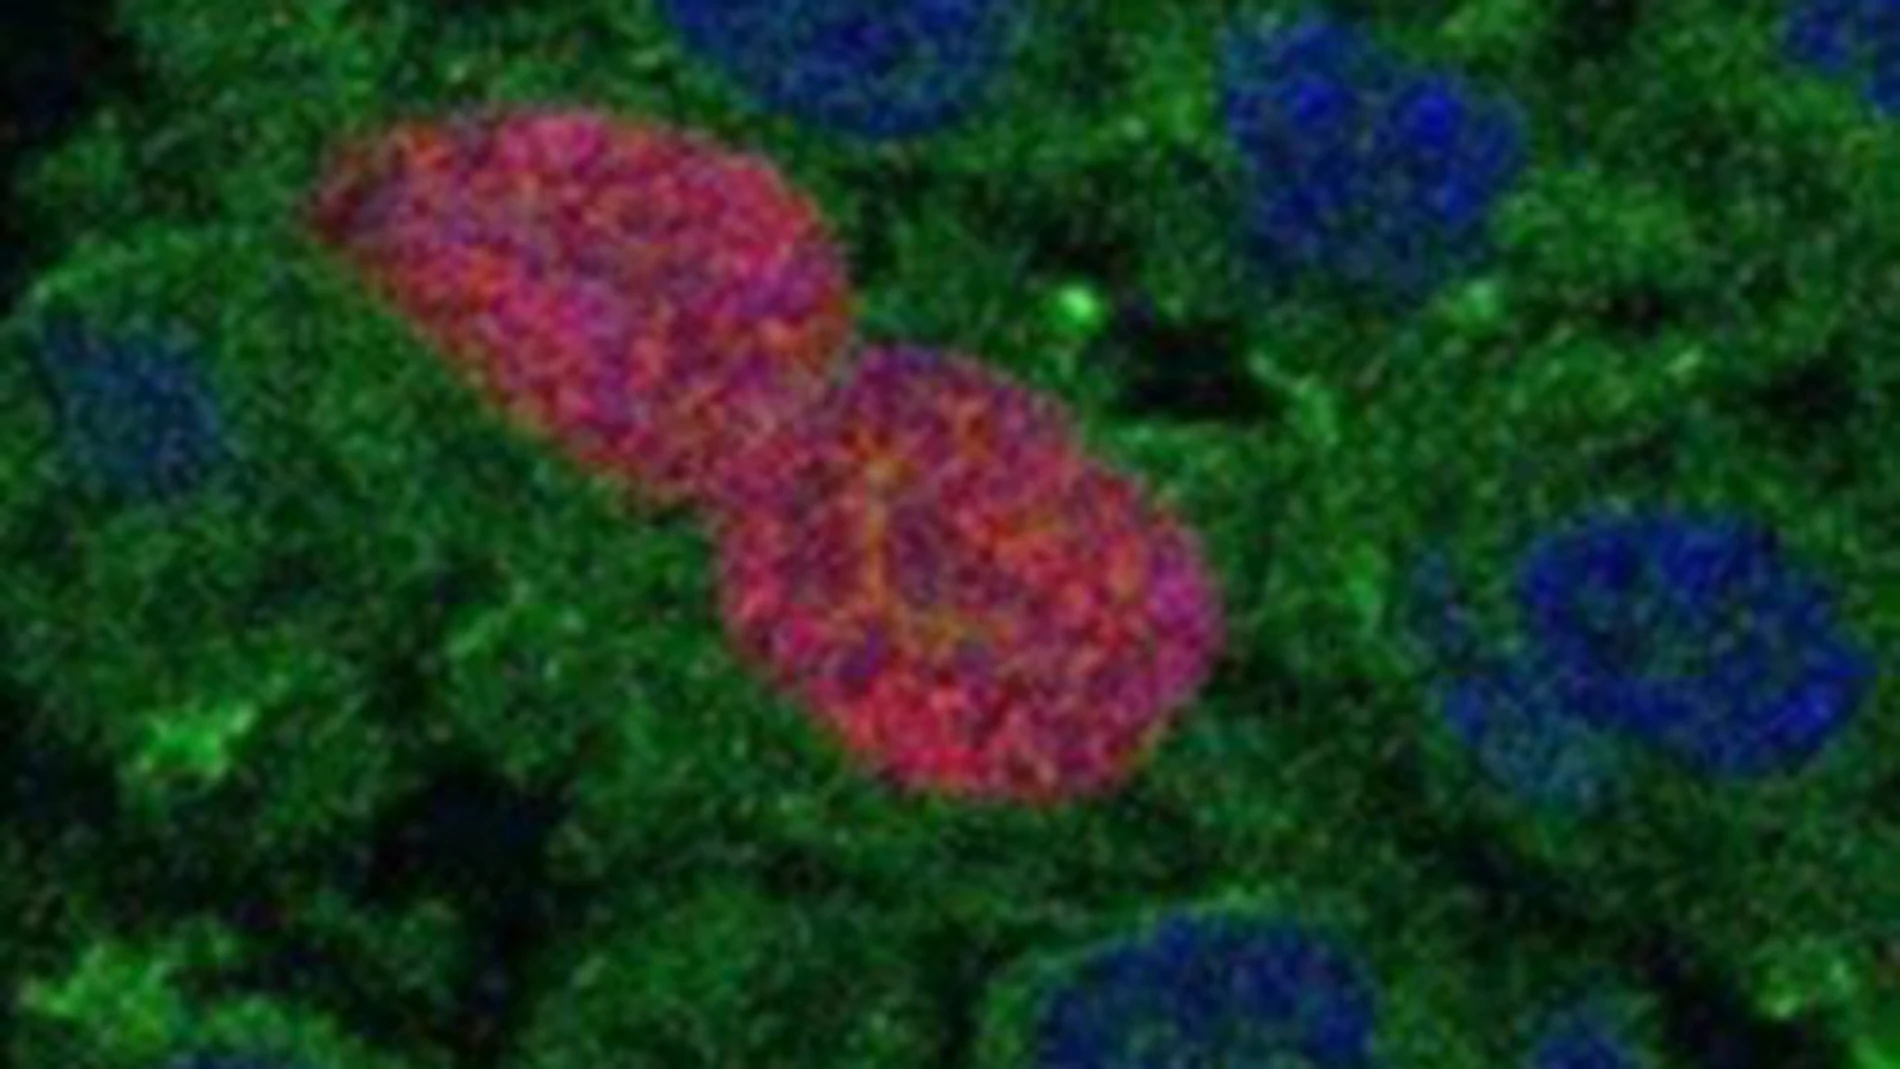

Los autores revelan que la presencia de AID en células epiteliales da lugar a la aparición de células pretumorales, con una alta tasa proliferativa y que acumulan mutaciones. Esto produce la activación de una respuesta inmune del organismo contra el daño en el ADN, principalmente a través de otro tipo de linfocitos, los linfocitos T citotóxicos, que destruyen las células pretumorales.

Según los expertos, es así como el sistema inmune detecta e impide que las células que presentan alteraciones en su ADN se expandan, evitando así que puedan generar un tumor.